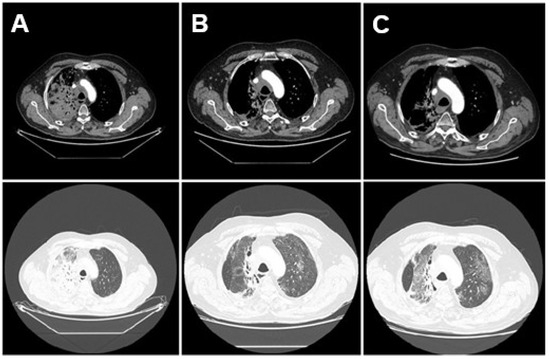

2. Case Presentation